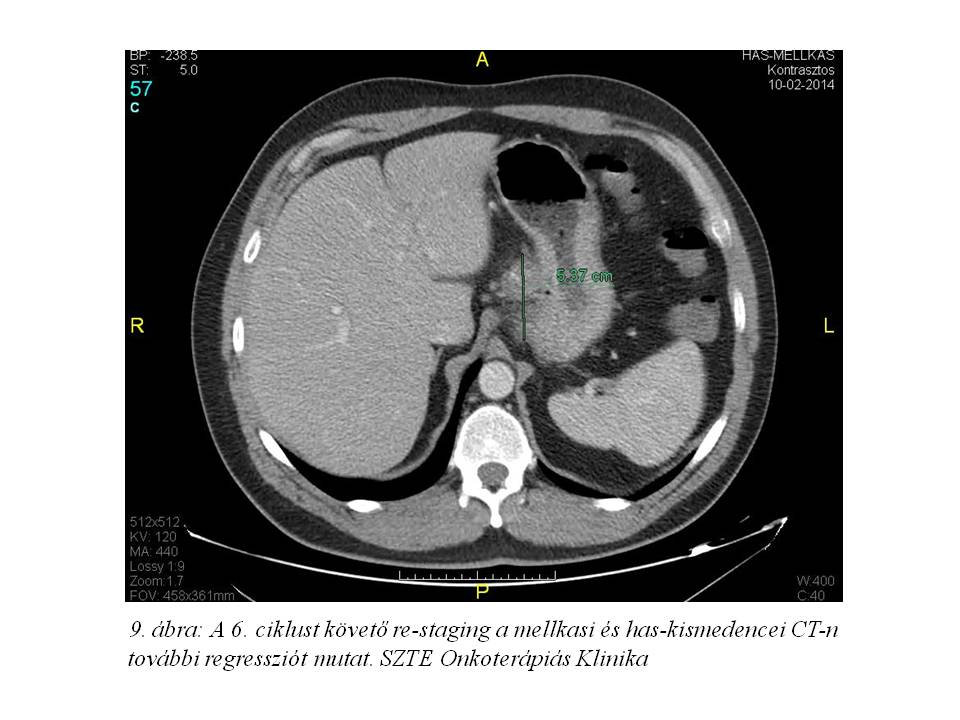

A 6. ciklust követően újabb mellkas, has-kismedence CT történt (2014.02.10. 9. ábra), mely további regressziót írt le. Ezt a kontroll gasztroszkópia is megerősítette. 2014.04.22-én exploratív laparotomia történt, azonban a nagyerekhez rögzült, nőiökölnyi konglomerátumot radikálisan eltávolítani nem lehetett, a tumort technikailag inkurábilisnek minősítették, tápláló jejunostomát készítettek.